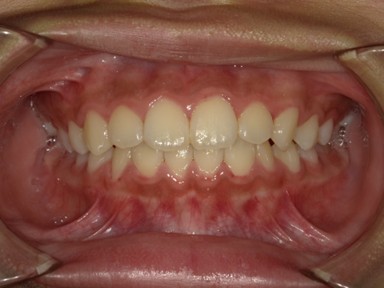

| 主訴 | 前歯が出ているので歯並びを良くしたい。 |

| 治療内容 | 使用装置:- マイオブレース(K1, K2, B1, K3) – 急速拡大装置 ・ワイヤー矯正:上顎前歯部(2-2)のみに2か月間使用 ・抜歯:なし |

| 治療期間 | 2020年2月~2023年1月(永久歯列完成まで観察) |

| 想定されたリスク | 全額ワイヤー治療になる可能性とそれに伴う歯根吸収のリスクがありました。 |

かみ合わせが非常に深く、下顎の成長を妨げておりました。扁桃腺の肥大が一因として考えられたため切除の提案をしました。マイオブレースを中心に、短期間のワイヤー治療でかみ合わせも健康面も良好になったかと思います。